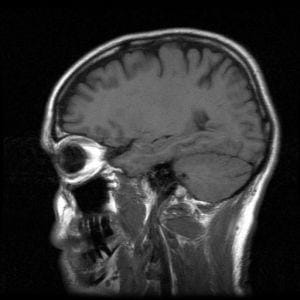

This lesson ties together the preceding lessons of this unit and brings students back to the overarching grand challenge question on MRI safety. During this lesson, students focus on the logistics of magnetic resonance imaging as well as MRI hardware. They integrate this knowledge with their acquired understanding of magnetic fields to create instructional safety awareness pamphlets, websites or slide presentations to solve the challenge question.Engineering Connection

Engineers developed the MRI as a non-invasive imaging method. During this lesson, students think like biomedical engineers to gain an understanding of the purpose of each aspect of the machine. Then students act as safety engineers, combining this information with their knowledge about magnetic fields to determine and communicate safety issues related to the MRI.

In order to solve the grand challenge and assess MRI safety issues, we must first learn how the MRI machine works. Then we can combine this knowledge with our understanding of magnetic fields to determine the safety issues with the MRI. Safety engineers are always looking for points of weakness in order to eliminate any potential safety hazards so medical equipment is safe for patients and medical staff.